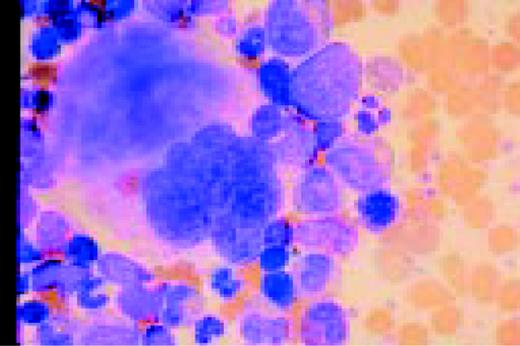

Slide L22

Hodgkin's disease, bone marrow aspirate. A classic binucleate Reed-Sternberg cell is seen in the center of the field, a rare finding in a bone marrow aspirate. The nuclei are mirror image, the nucleoli are large and there is intense cellular basophilia as well as marked cytoplasmic vacuolization.FIG22